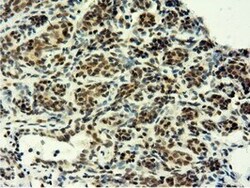

- Immunohistochemical staining of paraffin-embedded Carcinoma of Human lung tissue using anti-EPM2AIP1 mouse monoclonal antibody. (Heat-induced epitope retrieval by 10mM citric buffer, pH6.0, 100°C for 10min, TA501797)